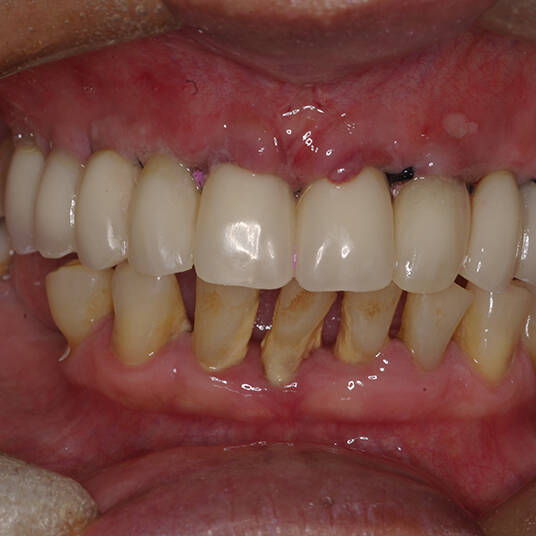

A Carga Imediata é uma técnica odontológica avançada que permite a colocação de uma prótese dentária fixa logo após a cirurgia de instalação dos implantes ou em poucos dias. Isso elimina a espera tradicional de meses para a integração completa do implante ao osso, oferecendo uma solução rápida e segura para restaurar dentes perdidos.

- Fixação da Prótese: Em até 72 horas após a cirurgia, a prótese provisória é instalada, permitindo que o paciente recupere a funcionalidade e a estética imediatamente.

- Conforto e Estética: A prótese provisória é funcional e visualmente semelhante aos dentes naturais.